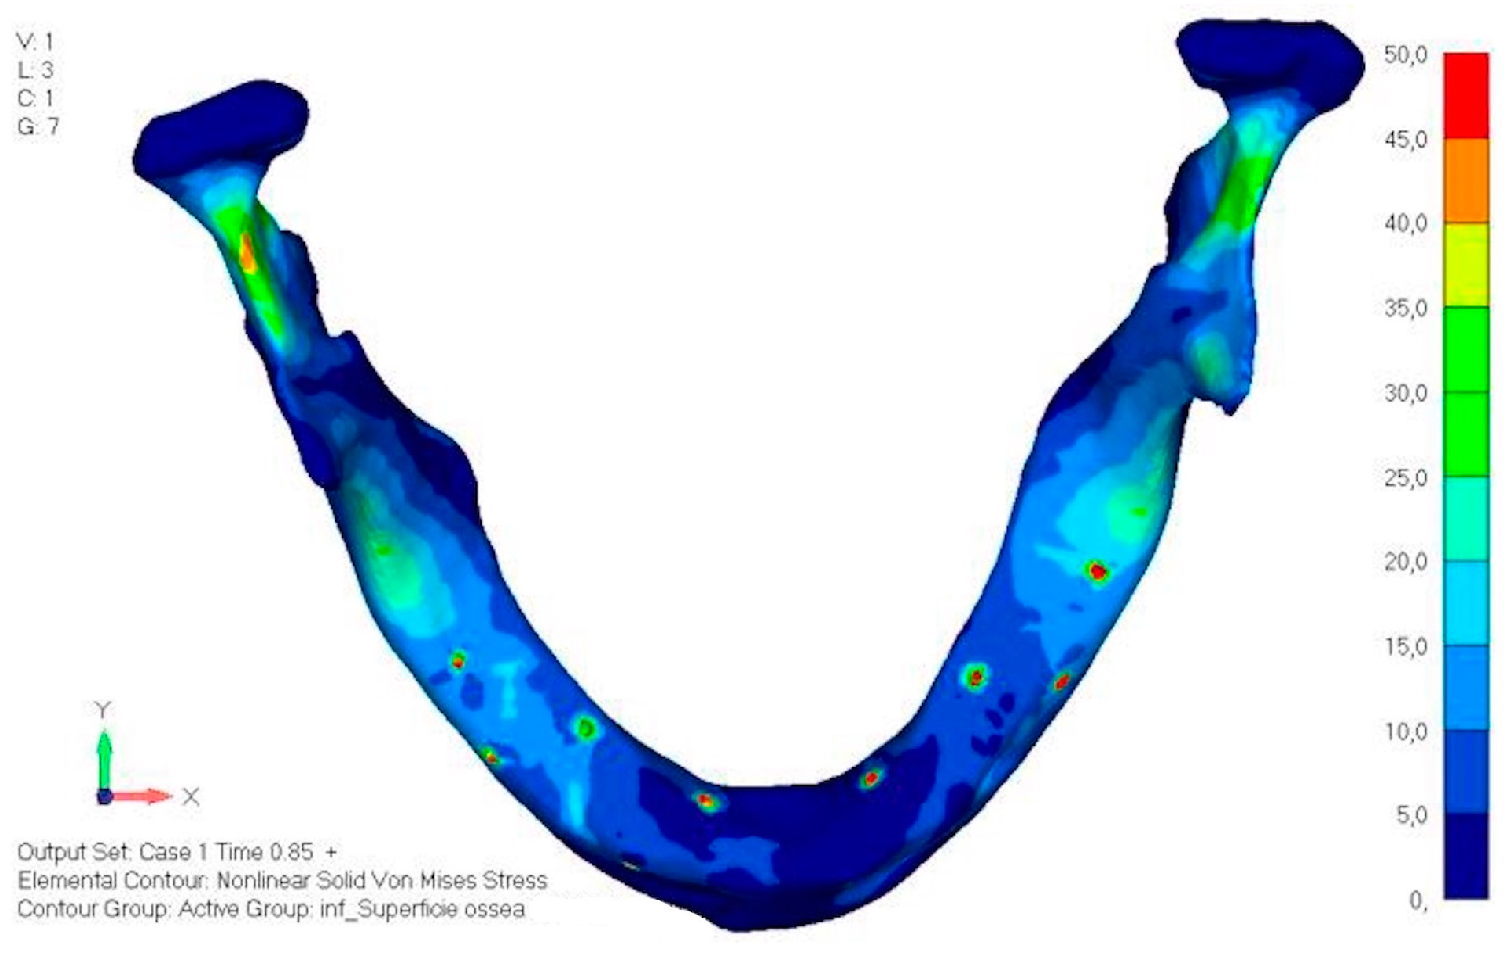

- Model V0. This model represents the initial analysis performed on the lower arch. The implant consists of two completely separate hemi-arches. The situation observed in the lower model is very similar to that found in the upper model. The most significant load is load 3 (Figure 20a,b), corresponding to chewing in the anterior right sector. Loads distributed over larger areas, such as configurations 1 and 2, result in less stress on both the implant and the bone (Figure 21 and Figure 22).

- Even in the lower model, the stresses observed in the peri-implant bone are always acceptable and significantly lower compared to those found in the upper implant. In the worst case, peak stresses reached 250 MPa, which ensures an adequate safety margin. From the bone perspective, in load configuration 3, it is noted that stresses exceed 50 MPa even in areas distant from the implant, such as near the condyles and in the posterior alveolar process.